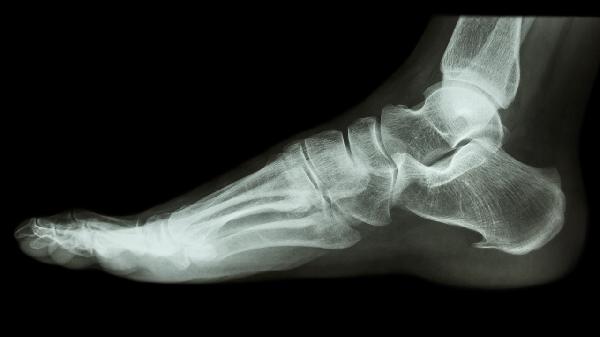

1、骨刺大小:

微小骨刺通过保守治疗可能在3-6个月缓解,直径超过5毫米的骨刺因机械刺激较强,往往需要6个月以上恢复。影像学检查显示骨刺尖端钝化是愈合的重要标志。